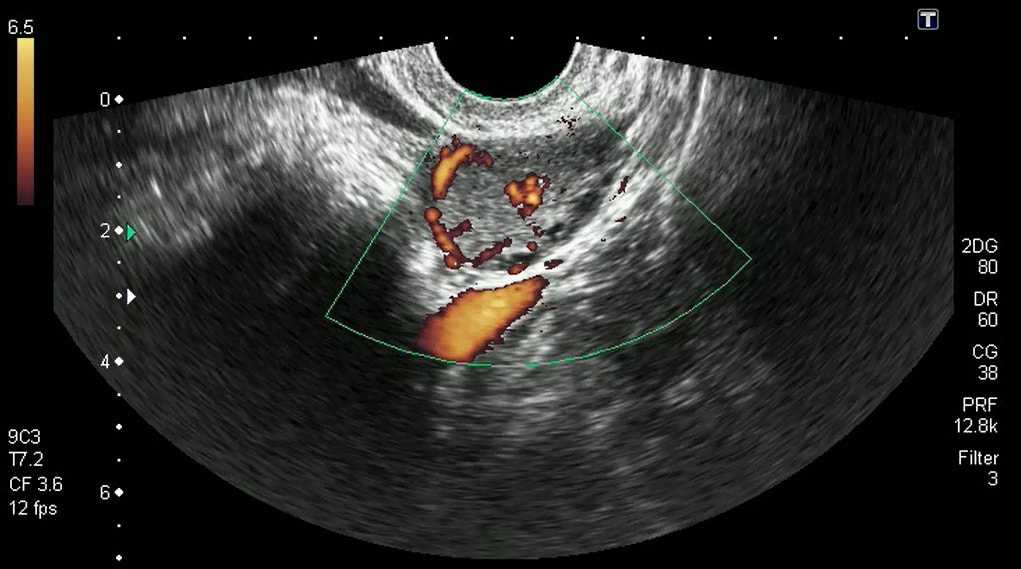

Фото УЗИ – фолликулометрии после овуляции. Есть жёлтое тело и свободная жидкость

Если всё прошло благополучно, на экране монитора можно увидеть:

- Жёлтое тело (округлое образование с неровными контурами) на месте созревшего фолликула. Размер жёлтого тела после овуляции (15 день цикла) — 15-20 мм. Оно активно растёт и достигает к 20 дню цикла диаметра 2,5-2,7 см. В течение недели после того как состоялась овуляция, жёлтое тело в яичнике угасает и исчезает в момент очередной менструации или наоборот — ещё активнее увеличивается (если произошло зачатие).

Жидкую субстанцию в дугласовом пространстве за маткой. Это содержимое доминантного фолликула, которое вытекает после освобождения зрелой яйцеклетки, и небольшая часть секрета фаллопиевых труб.

Если состоялась овуляция, жидкость в позадиматочном пространстве скапливается в незначительном объёме. В норме её вертикальный уровень менее 10 мм, если же он превышает 50 мм, это может быть следствием различных патологических процессов во внутренних половых органах.